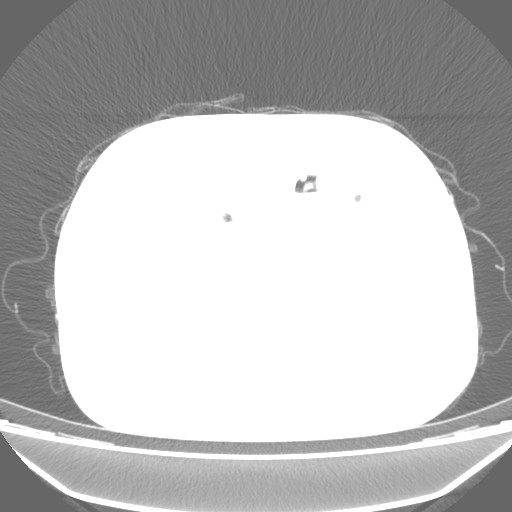

Bu da çekilen BT sanırım, gördükleriniz neyi ifade ediyor? Yanlış görüntüleri attıysam kusura bakmayın internetteki gibi akciğerin düz göründüğünü gördüğüm fotoğraf yoktu. Gerçekten 1 yıldan fazla süren geçmeyen öksürük, üst solunum yolu enfeksiyonu denilen bir hastalık varsa ve bu 3 haftada geçebiliyorsa, nasıl oluyor da hastalığı bu olabilir?

Bu da başka bir değer sanırım ama gözüküyor mu lekeler bilmiyorum, fotoğraf indirirken de böyle küçük ve kalitesiz geldi biraz.

Bu da lekelerin gözüktüğü, tam olarak anlamadım ve e-Devlet'te de aynı bu vardı başta. Bir sürü resim var, acaba size ZIP olarak hepsini göndersem baksanız? Çünkü internetteki gibi BT değil, farklı bir çekim mi acaba bu, belki de başka bir organdır? Özel bilgiler var mıdır ZIP'in içerisinde hepsini atmam problem olur mu? Baktığım fotoğraflar genellikle hep aynı, seri değişince değişiyor. Bazıları Full beyaz görüntü. İlk defa baktığım için yanlış bir şey attıysam kusura bakmayın. Bu fotoğrafları e-Devlet'in radyolojik yerinden aldım, e postaya yolladım.

Bu da çekilen BT sanırım, gördükleriniz neyi ifade ediyor? Yanlış görüntüleri attıysam kusura bakmayın internetteki gibi akciğerin düz göründüğünü gördüğüm fotoğraf yoktu. Gerçekten 1 yıldan fazla süren geçmeyen öksürük, üst solunum yolu enfeksiyonu denilen bir hastalık varsa ve bu 3 haftada geçebiliyorsa, nasıl oluyor da hastalığı bu olabilir?

Bu da başka bir değer sanırım ama gözüküyor mu lekeler bilmiyorum, fotoğraf indirirken de böyle küçük ve kalitesiz geldi biraz.

Bu da lekelerin gözüktüğü, tam olarak anlamadım ve e-Devlet'te de aynı bu vardı başta. Bir sürü resim var, acaba size ZIP olarak hepsini göndersem baksanız? Çünkü internetteki gibi BT değil, farklı bir çekim mi acaba bu, belki de başka bir organdır? Özel bilgiler var mıdır ZIP'in içerisinde hepsini atmam problem olur mu? Baktığım fotoğraflar genellikle hep aynı, seri değişince değişiyor. Bazıları Full beyaz görüntü. İlk defa baktığım için yanlış bir şey attıysam kusura bakmayın. Bu fotoğrafları e-Devlet'in radyolojik yerinden aldım, e postaya yolladım.